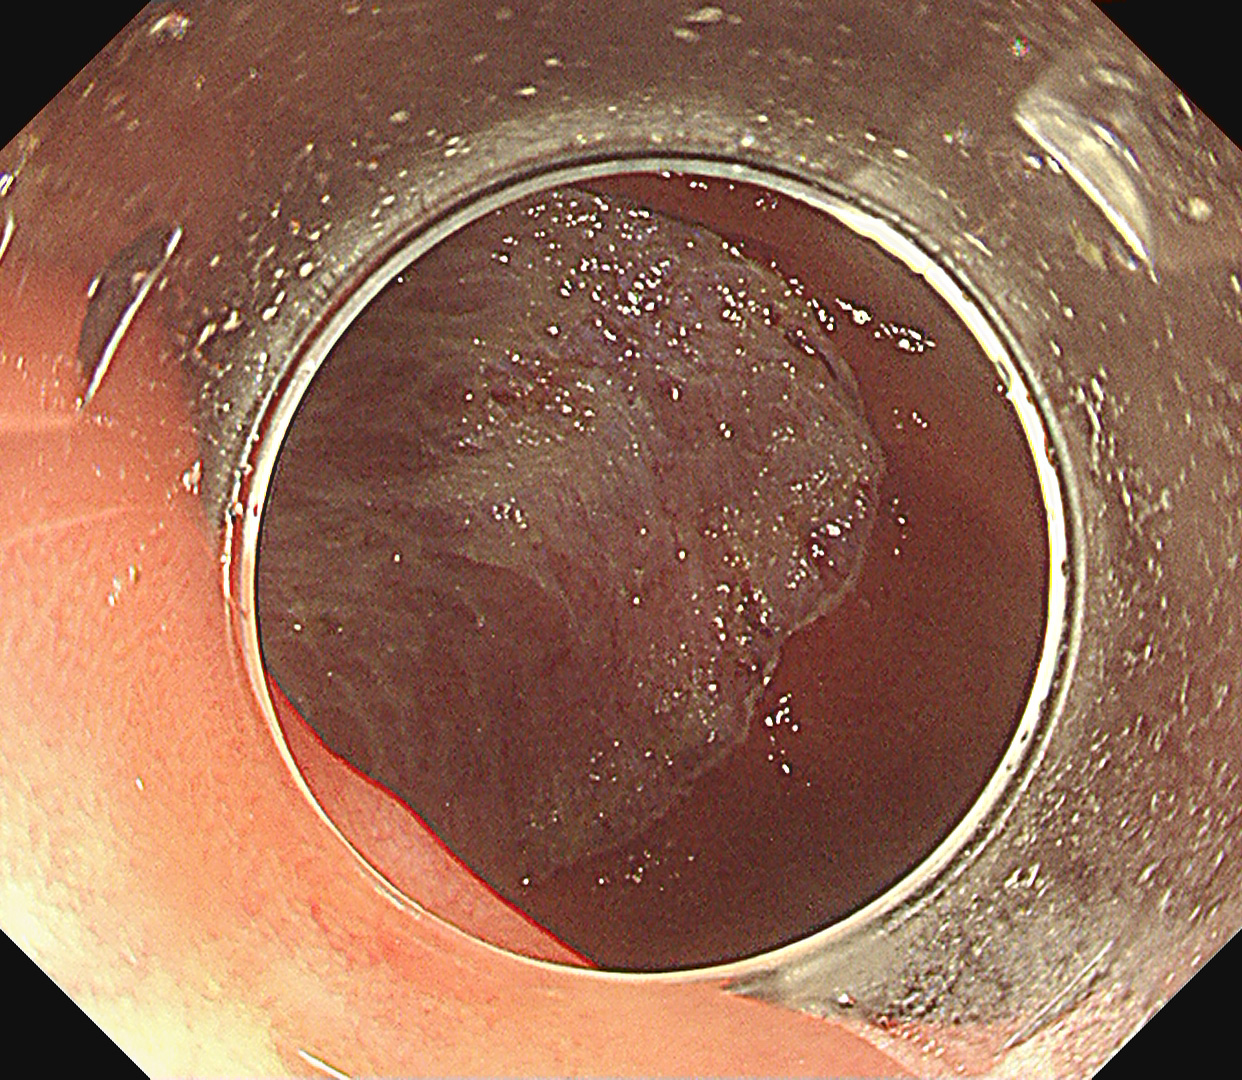

- EMR・ESD による早期消化管癌の低侵襲治療

早期大腸癌(LST-G)ESD